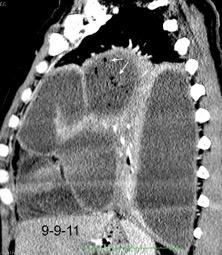

Marzo 2014: Perforación longitudinal distal secundaria a episodio de vómito (síndrome de Boerhaave). Derrame pleural izdo. que evoluciona a empiema.

Wang C-T et al. Tension hydropneumothorax in a Boerhaave syndrome patient: A case report . World J Emerg Med, 2021. Katabathina V et al. Nonvascular, nontraumatic mediastinal emergencies in adults:a comprehensive review of imaging findings. Radiographics. 2011.